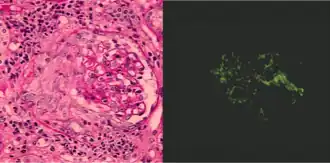

Como ya se dijo, la glomerulonefritis puede tener una patogenia inmune o inflamatoria y aunque en algunas situaciones es posible establecer un diagnóstico específico sobre la base de la presentación clínica y las pruebas de laboratorio, en la mayor parte de los casos es útil realizar una biopsia renal tanto para efectuar la clasificación como para determinar el pronóstico. Además, lo ideal es que las muestras de biopsia se examinen con el microscopio óptico, mediante inmunofluorescencia y por microscopia electrónica porque ese enfoque permitirá diagnosticar el patrón histológico. En algunos casos ese patrón se puede comparar con los resultados de otras pruebas de laboratorio para identificar una etiología específica, pero en muchos otros la enfermedad es idiopática. Aun así, como los tratamientos suelen desarrollarse para patrones histológicos específicos, en el manejo actual de estos trastornos se prefiere este enfoque.[7]

Histopatología

La evaluación histopatológica completa de las muestras obtenidas para la biopsia renal requiere el empleo de microscopia óptica y electrónica y el examen con las técnicas de inmunofluorescencia o inmunoperoxidasa para detectar depósitos de complemento e inmunoglobulina.[7]

Técnicas con inmunofluorescencia e inmunoperoxidasa

Para identificar fenómenos reactivos inmunitarios se utilizan inmunofluorescencia indirecta y tinción con inmunoperoxidasa. La tinción se usa para detectar IgG, IgA e IgM, componentes del sistema del complemento (habitualmente C3, C4 y Clq) y fibrina, que suele verse en las semilunas y en los capilares en los trastornos trombóticos (como el síndrome urémico hemolítico y el síndrome antifosfolípidos). Puede haber depósitos inmunes a lo largo de las asas capilares o en el mesangio y es posible que sean continuos (lineales) o discontinuos (granulares).[7]

El mejor método para el diagnóstico de las enfermedades renales de etiología inmunitaria consiste en realizar la biopsia renal y estudiar con microscopia óptica los tejidos teñidos porque de ese modo se podrá anticipar el pronóstico y seleccionar el tratamiento adecuado. Sin embargo, como hay varios mecanismos inmunitarios que pueden provocar cambios morfológicos similares, también resulta útil la microscopia de inmunofluorescencia con anticuerpos específicos marcados con fluoresceína para determinar el tipo y la localización de los compuestos inmunes en el riñón.[17] Además, la biopsia renal es importante porque no solo permite saber dónde se encuentra la lesión histológica o qué mecanismos intervienen sino también el grado de importancia de dicha lesión, un factor fundamental para decidir qué tipo de manejo terapéutico se requiere y en qué momento iniciarlo.[16]